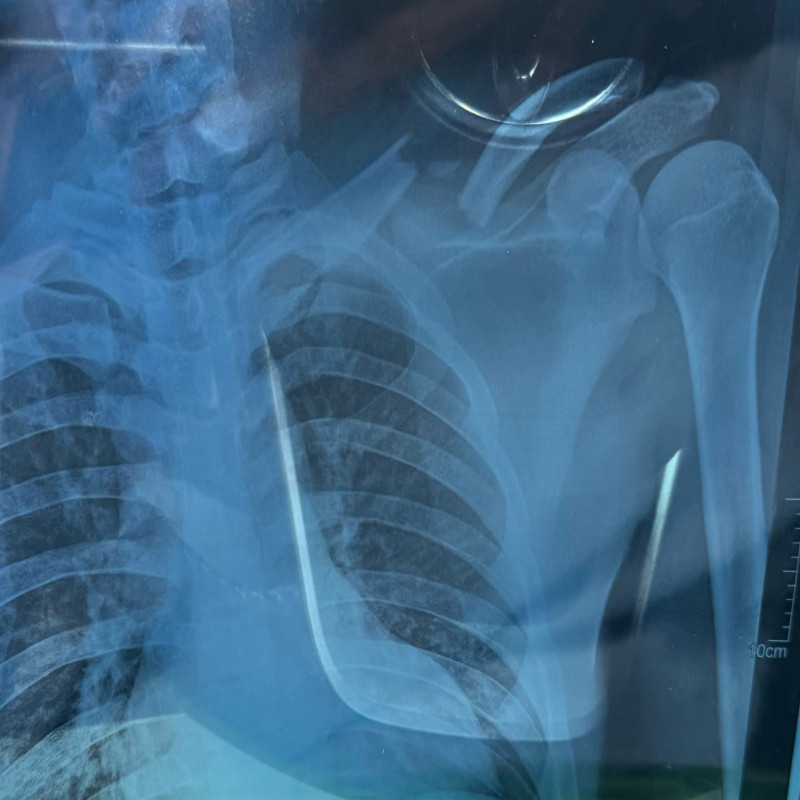

Dari hasil scan, terlihat bahu kiri patah (fraktur

clavicula) sehingga diperlukan untuk dibawa ke RS yang lebih memadai untuk tindakan

operasi sehingga dibawalah ke RS Mitra Keluarga Tegal dan dilakukan operasi